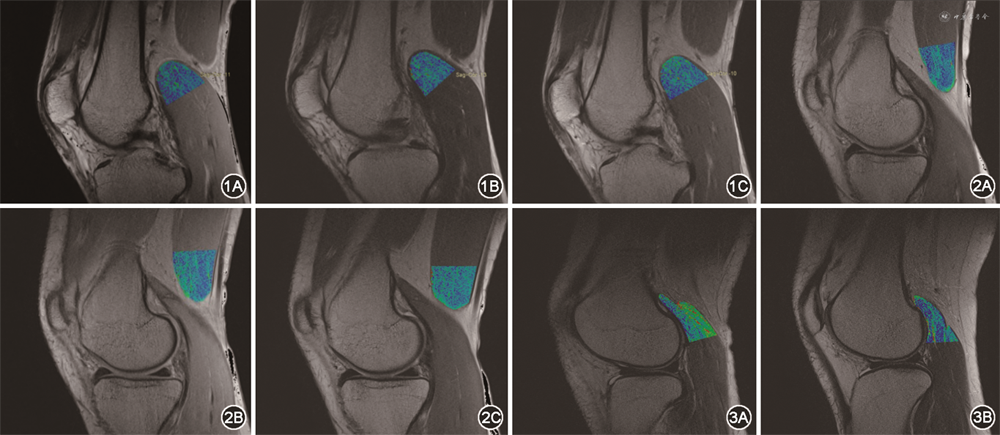

在T2弛豫时间参数图伪彩图与解剖图的融合图像上,色阶信号由蓝到绿到红代表T2值逐渐升高。对比马拉松组赛前、赛后腓肠肌内侧头和半膜肌的T2值变化特征,腓肠肌内侧头的T2值呈先上升后下降的趋势,在色阶图像上表现为赛前腓肠肌内侧头感兴趣区内整体呈蓝色色阶信号,赛后12 h内绿色色阶信号明显增加,可见部分红色信号,赛后2个月绿色信号较赛后12 h内稍减少,较赛前仍明显增加(图1);半膜肌的T2值呈先上升后水平的趋势,在色阶图像上表现为赛前半膜肌感兴趣区内大部分为蓝色信号,仅中间部分呈现绿色信号;赛后感兴趣区内绿色信号明显增加(图2)。对比马拉松组赛前与对照组腓肠肌外侧头T2值变化特征,马拉松组腓肠肌外侧头的T2值低于对照组,在色阶图像上表现为健康志愿者的腓肠肌外侧头整体呈绿色色阶信号,以浅层为著,另可见部分红色信号;而业余马拉松运动员的腓肠肌外侧头信号较健康志愿者明显减低,色阶信号整体呈蓝色(图3)。